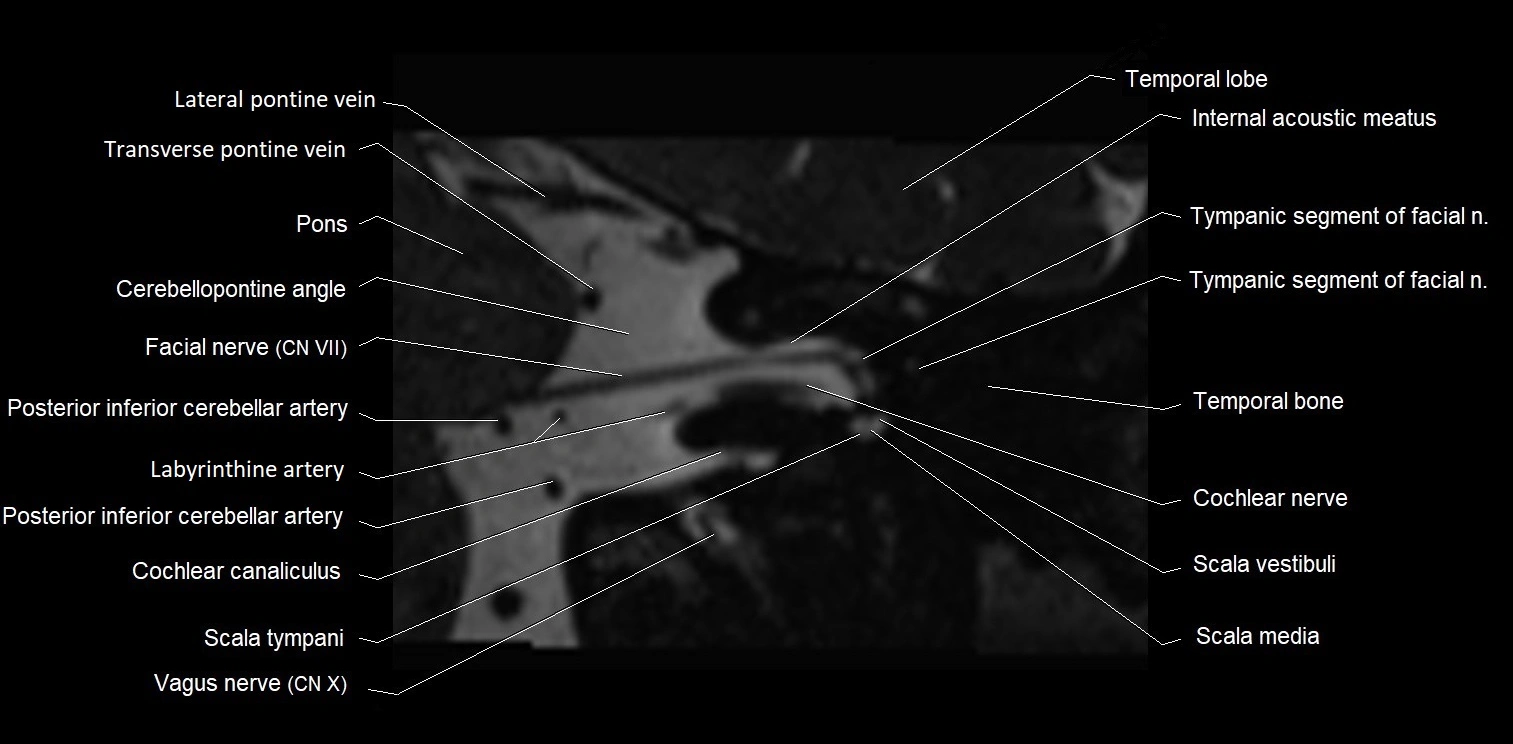

MRI images

image